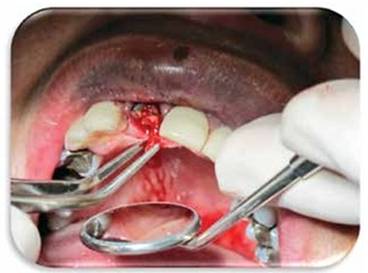

Se realiza control 1 mes despúes y se determina que es necesario rea- lizar una fibrotomía para ayudar en el proceso de extrusión rápida. (Figura 11)

Se hace una fibrotomía para ayudar al proceso y se deja ferulizado por 4 meses. (Figura 12)

Figura 12: Se muestra la hoja de bisturí aplicada al periodonto para poder realizar la fibrotomía.